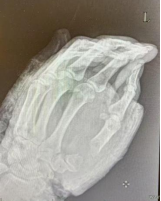

術(shù)后72小時(shí)是斷指再植血管危象高發(fā)窗口,手術(shù)團(tuán)隊(duì)沒(méi)有松懈,密切觀察殘端血運(yùn),1周后殘端血運(yùn)如常,整個(gè)團(tuán)隊(duì)終于松了口氣,度過(guò)了血管危象和感染,術(shù)后1周患者順利出院。但手術(shù)團(tuán)隊(duì)仍與患者保持密切聯(lián)系,術(shù)后2周拆線。前幾日復(fù)查x線,骨折端復(fù)位滿意,拆除外固定支架。并詳細(xì)指導(dǎo)功能鍛煉,李師傅及家屬對(duì)治療效果非常滿意。